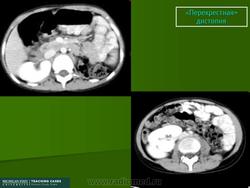

Перекрестная дистопия почки

Перекресная дистопия почки встречается редко и характеризуется перемещением одной из почек за срединную линию тела. Таким образом, обе почки оказываются по одну сторону позвоночника. Очень часто обе почки срастаются в один орган, но при этом имеют каждая собственные сосуды и мочеточники. Обычно такая аномалия не проявляется клинически и ее диагностируют при помощи ультразвукового исследования и экскреторной урографии. Оперативное лечение проводят только если возникает заболевание, требующее оперативного вмешательства (гидронефроз, опухоль, мочекаменная болезнь, пиелонефрит).